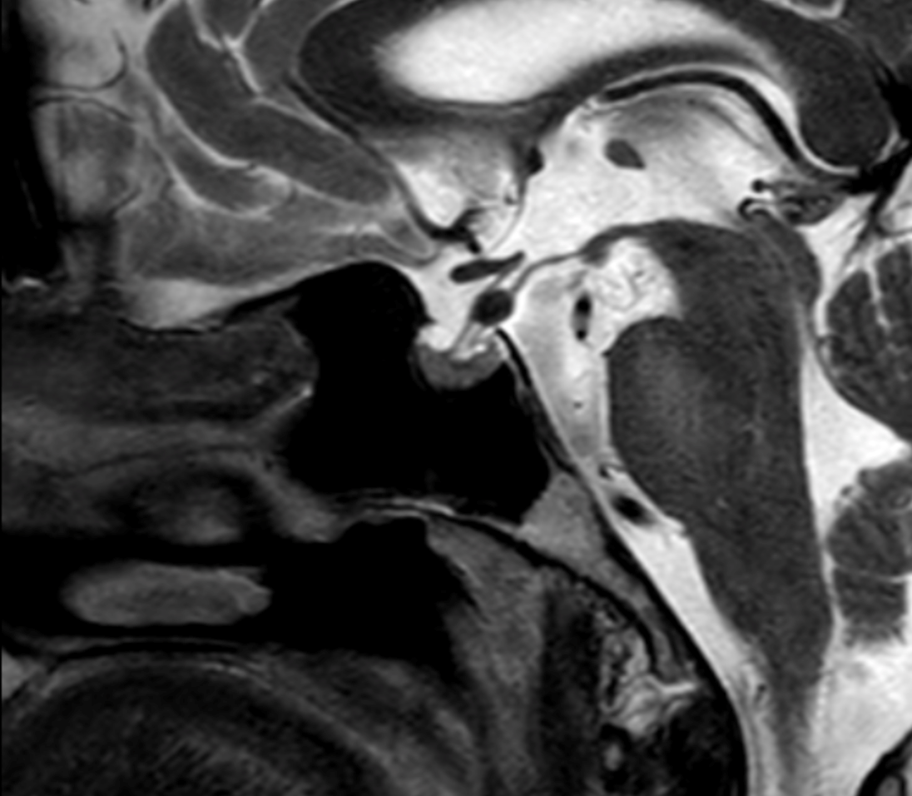

A 24-year-old woman, known for asthma and pre-diabetes, presented to the ER 8 days post-partum with frontal and retro-orbital headaches, bilateral lower limb paresthesia and gait instability. Her pregnancy and delivery history were unremarkable except for gestational diabetes treated with insuline and peri-partum fever.

She complained of subacute onset of numbness in her tongue, bilaterally on her face and distally in her lower limbs without any weakness. Initial neurological exam was essentially normal.  Initial workup and brain and spine CT Scans were normal.

2 days after admission, she rapidly developed bilateral facial palsy. A repeated neurological exam confirmed the bilateral peripheral facial nerve palsy with marked Bell’s phenomenon and secondary dysarthria but no dysphagia. The motor exam was normal. The sensitive exam was remarkable for variable patches of pinprick hypoesthesia, non-congruent with radicular or peripheral nerve territories. Deep tendon reflexes were absent in the right lower limb, which was new. Several investigations including a brain MRI, lumbar puncture and an electrodiagnostic study were obtained.

Investigations

• CBC, Liver function, renal function, electrolytes: normal

• C-reactive protein: mildly elevated at 21.2 mg/L

• Lumbar puncture: WBC 1, RBC 44, protein 1.88 g/L; CSF culture, PCR for HSV-1, HSV-2, Listeria monocytogenes, VZV were negative

• Microbiology/Virology: PCR negative for CMV, EBV; HIV, syphilis and Lyme testing were negative

• Serum antiganglioside panel still pending

• Normal thorax CT and normal angiotensin conversion enzyme

• Normal brain MRI with contrast and normal complete spine MRI

• EMG was performed a month after symptom onset (cf. figure 1)